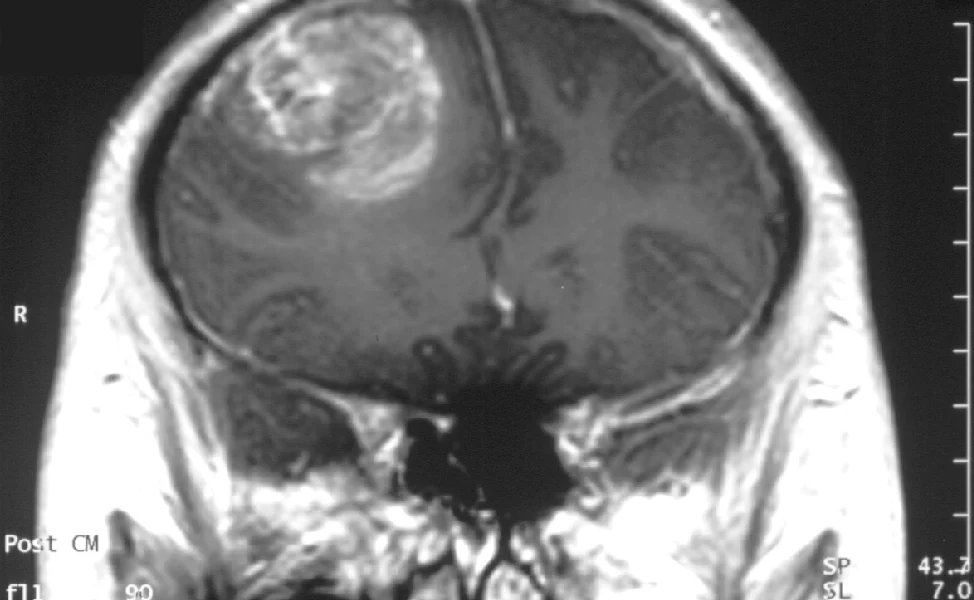

Kanados mokslininkai atrado netikėtą glioblastomos, vienos iš pavojingiausių smegenų vėžio formų, silpnybę. Tyrimo metu nustatyta, kad tam tikros smegenų ląstelės, anksčiau laikytos tik normalios nervų funkcijos palaikytojomis, gali iš tikrųjų padėti navikams augti, siųsdamos signalus, kurie stiprina vėžio ląsteles. Blokuojant šią komunikaciją laboratoriniais modeliais, naviko augimas dramatiškai sulėtėjo.

Mokslininkai ilgą laiką žinojo, kad glioblastomos augimui reikalingi tarpusavyje bendraujančių ląstelių tinklai. Šio tyrimo tikslas buvo nustatyti, kurios konkrečios smegenų ląstelės dalyvauja šiame procese. Tyrėjai nustatė, kad oligodendrocitai, kurie paprastai saugo nervų skaidulas, gali pakeisti savo elgesį ir pradėti palaikyti navikų augimą. Šios ląstelės bendrauja su vėžio ląstelėmis per aiškiai apibrėžtą signalizacijos sistemą, kuri sukuria sąlygas, leidžiančias navikui išgyventi ir plėstis. Kai ši signalizacija buvo blokuota laboratoriniuose modeliuose, naviko augimas žymiai sulėtėjo, parodydamas, kiek svarbi yra ši sąveika.